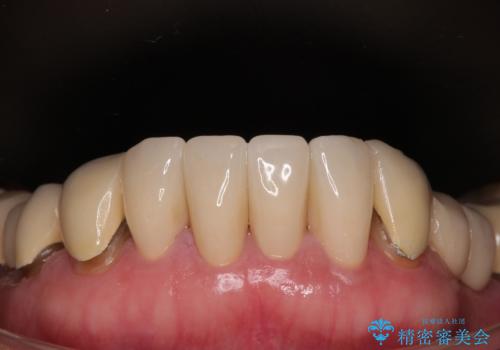

【海外から通院】統一感のない前歯をきれいに オールセラミッククラウン治療

臼歯部の治療も必要と判断されましたが、前歯部を中心とした審美領域をオールセラミッククラウンによる補綴治療を行うこととしました。

帰国時のみの治療であったため、治療期間は長くなりましたが、最小限の来院回数で、気になっていた前歯をきれいに整えることができました。